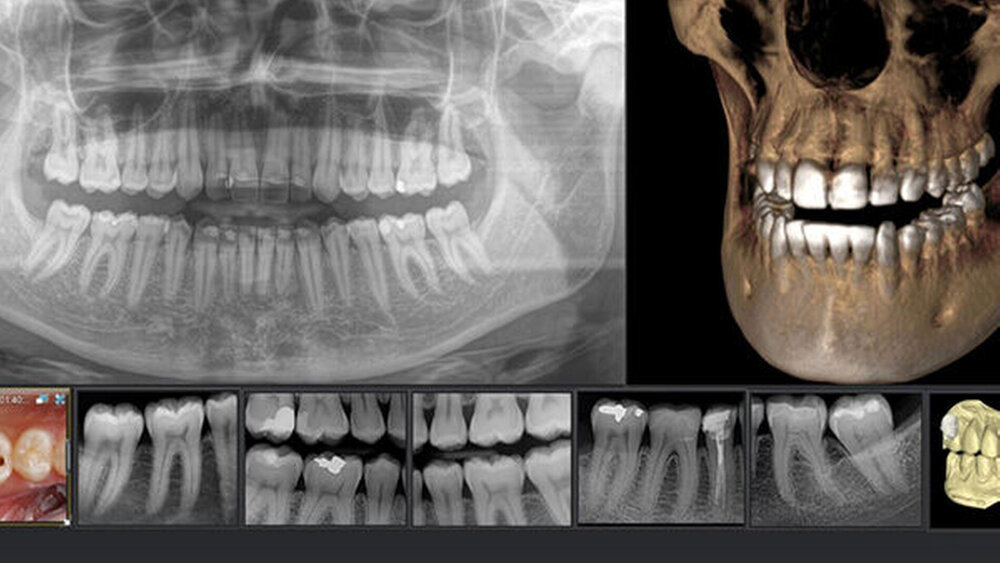

Wer jetzt von Sidexis XG auf die aktuelle Version (4.3.1) von Sidexis 4 upgraden möchte, wird einen Quantensprung erleben. Im modernen und intuitiven Design strukturiert die Röntgensoftware den Workflow effizient und dient als Knotenpunkt für die weitere Planung und Befundung. Die mehrfach preisgekrönte Nutzeroberfläche ist extrem einfach zu bedienen. Der digitale Leuchtkasten stellt sowohl 2D- als auch 3D-Aufnahmen nahtlos in einer Software-Oberfläche dar. So ist beispielsweise ein schneller und unproblematischer Quervergleich einer Intraoralaufnahme mit einem 3D-Scan möglich. Die Timeline-Funktion gibt einen praktischen Überblick über die gesamte Patientenhistorie und bereichert die Diagnosemöglichkeiten ganz intuitiv um eine zeitliche Dimension.